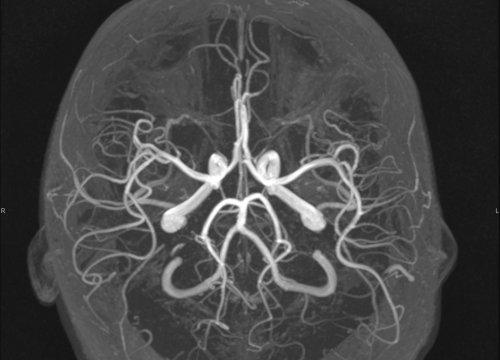

FOTO Ako su vam potrebni specijalistički pregledi mamografija, RTG, UZV, CT i MR, koji se inače koriste za dijagnostiku velikog broja zdravstvenih problema, možete ih obaviti već danas ili sutra. Vodite računa o vašem zdravlju i zakažite pregled u Poliklinici Affidea Vita u Šibeniku na vrijeme!